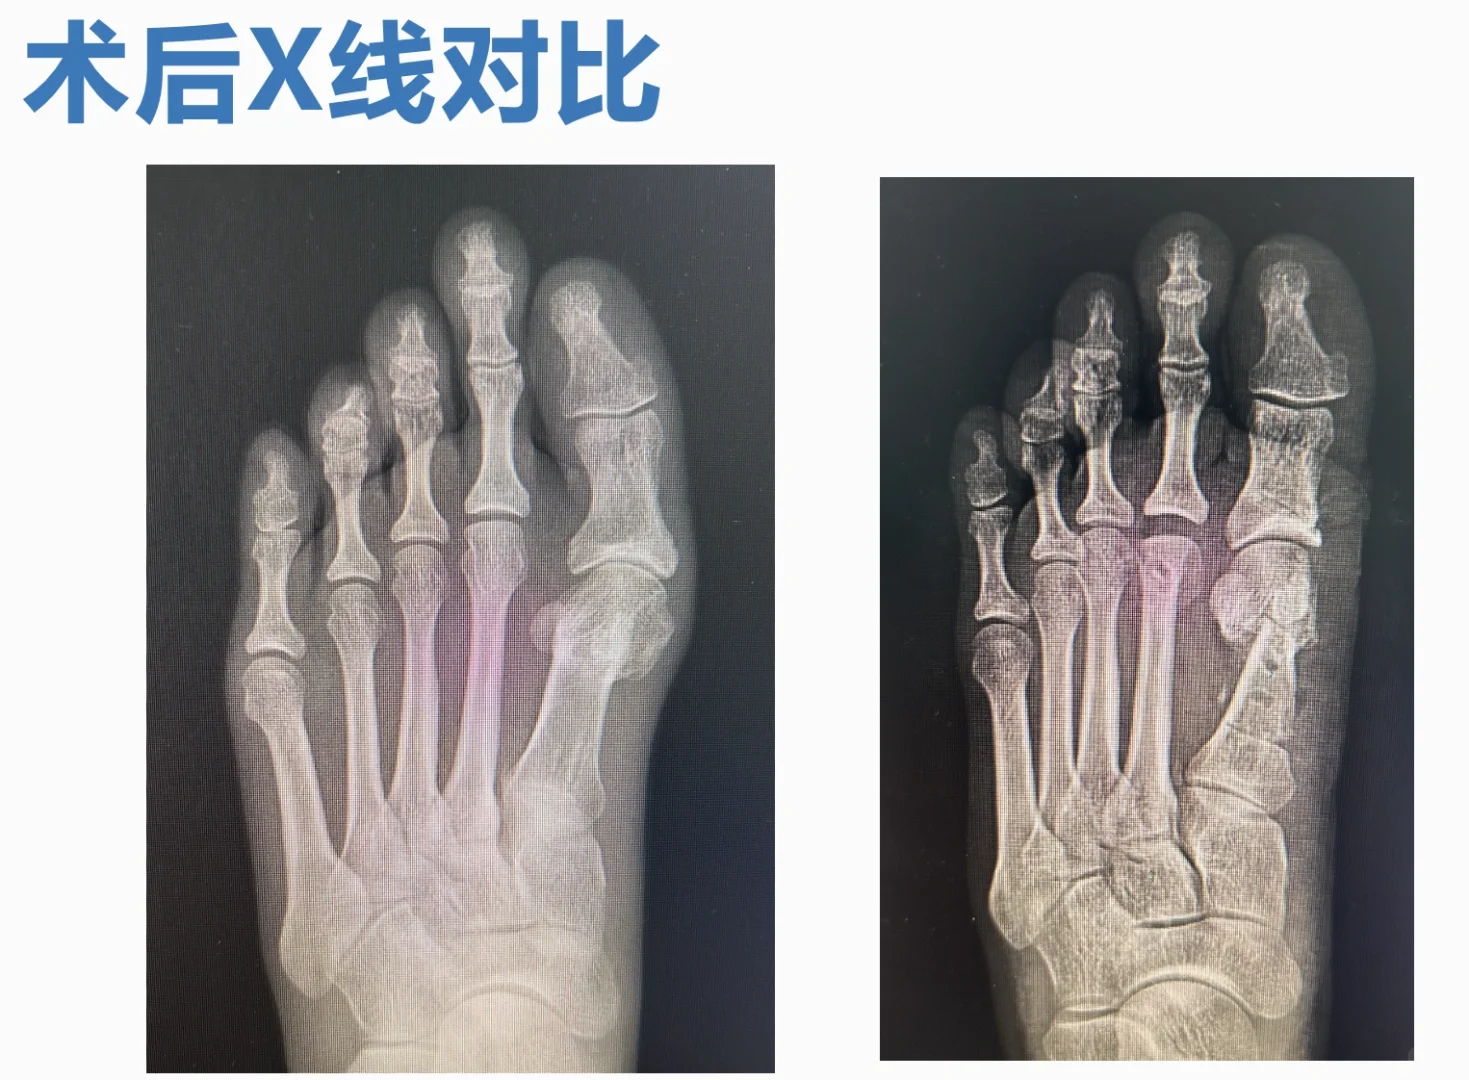

翻修的越来越多,难度也越来越大,但是,经验也越来越多。 微创术后的三种特殊畸形,已经彻底搞定了一种,还有一种在研究,另一种因为关节的毁损,目前看只能等人工关节了。 然而,大量的假患者仍然遍布这个平台。 翻修不光是外观问题,关节软骨、血运、长短、高低、旋转,一般讲,绝大部分无法恢复正常结构,只能针对症状处理了。